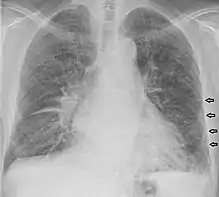

خطوط كيرلي (بالإنجليزية: Kerley lines) هي علامة شعاعية ترى عند تصوير الصدر بالأشعة السينية ذا الوذمة الرئوية الخلالية. إنها عتامة رئوية خطية رقيقة ناتجة عن تسلل سائل أو خلوي إلى الخلال الرئوي. سميت على اسم أخصائي الأعصاب الإيرلندي بيتر كيرلي.[1][1]

هي خطوط متوازية قصيرة في محيط الرئة. تمثل هذه الخطوط الحاجز الحُبيبي (بين فصوص الرئة)، الذي عادة ما يكون طوله أقل من 1 سم وموازيًا لبعضهما البعض في الزوايا اليمنى لغشاء الجنب. تقع في محيطها على اتصال مع غشاء الجنب، لكنها غائبة على السطوح الانشطارية. يمكن رؤيتها في أي منطقة ولكن يتم ملاحظتها بشكل متكرر في قواعد الرئة عند "الردب الضلعي الحجابي" في صورة شعاعية بانورامية، وفي المنطقة الفرعية على الصور الشعاعية الجانبية.[2] تشمل أسباب خطوط كيرلي ب الوذمة الرئوية، وسرطان الغدد الليمفاوية، وسرطان الغدد الليمفاوية الخبيثة، والالتهاب الرئوي الفيروسي، والميكلوبلاسي، والتليف الرئوي الخلالي، والتهاب الرئة وساركويد. يمكن أن تكون علامة زائدة على صورة الصدر بالأشعة السينية للمريض داخل وخارج القلب.